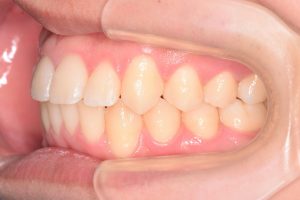

2期治療開始時(2023年7月)と装置撤去時(2025年9月)の写真です。

左側